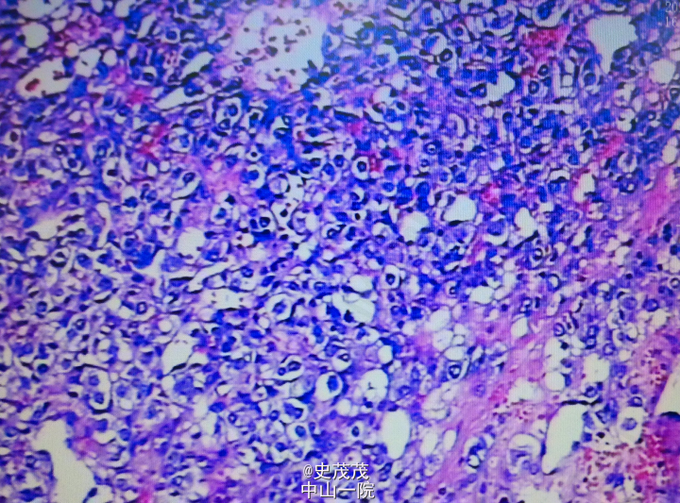

病理:镜检肿物可见纤维性包裹,肿瘤细胞实性片状分布,瘤细胞界清,胞质嗜碱性,核椭圆形,见凝固性坏死,核分裂偶见。IHC:CgA+、NSE+、Ki67阳性率约2%、CK-。结合HE及免疫组化,病变考虑为嗜铬细胞瘤。